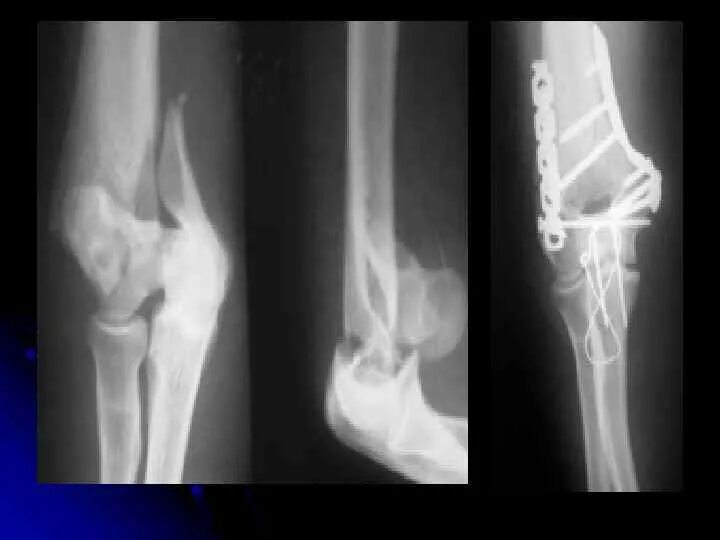

Как разрабатывать руку перелом локтевого сустава